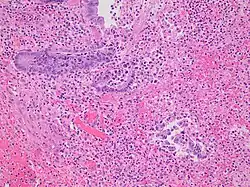

Even for clinically certain appendicitis, routine histopathology examination of appendectomy specimens is of value for identifying unsuspected pathologies requiring further postoperative management.[75] No sign of appendicitis in specimens, negative appendectomy, varies but has been estimated to occur in 13% of specimens.[76] Notably, appendix cancer is found incidentally in about 1% of appendectomy specimens.[77][78]

Pathology diagnosis of appendicitis can be made by detecting a neutrophilic infiltrate of the muscularis propria.

Periappendicitis (inflammation of tissues around the appendix) is often found in conjunction with other abdominal pathology.[79]